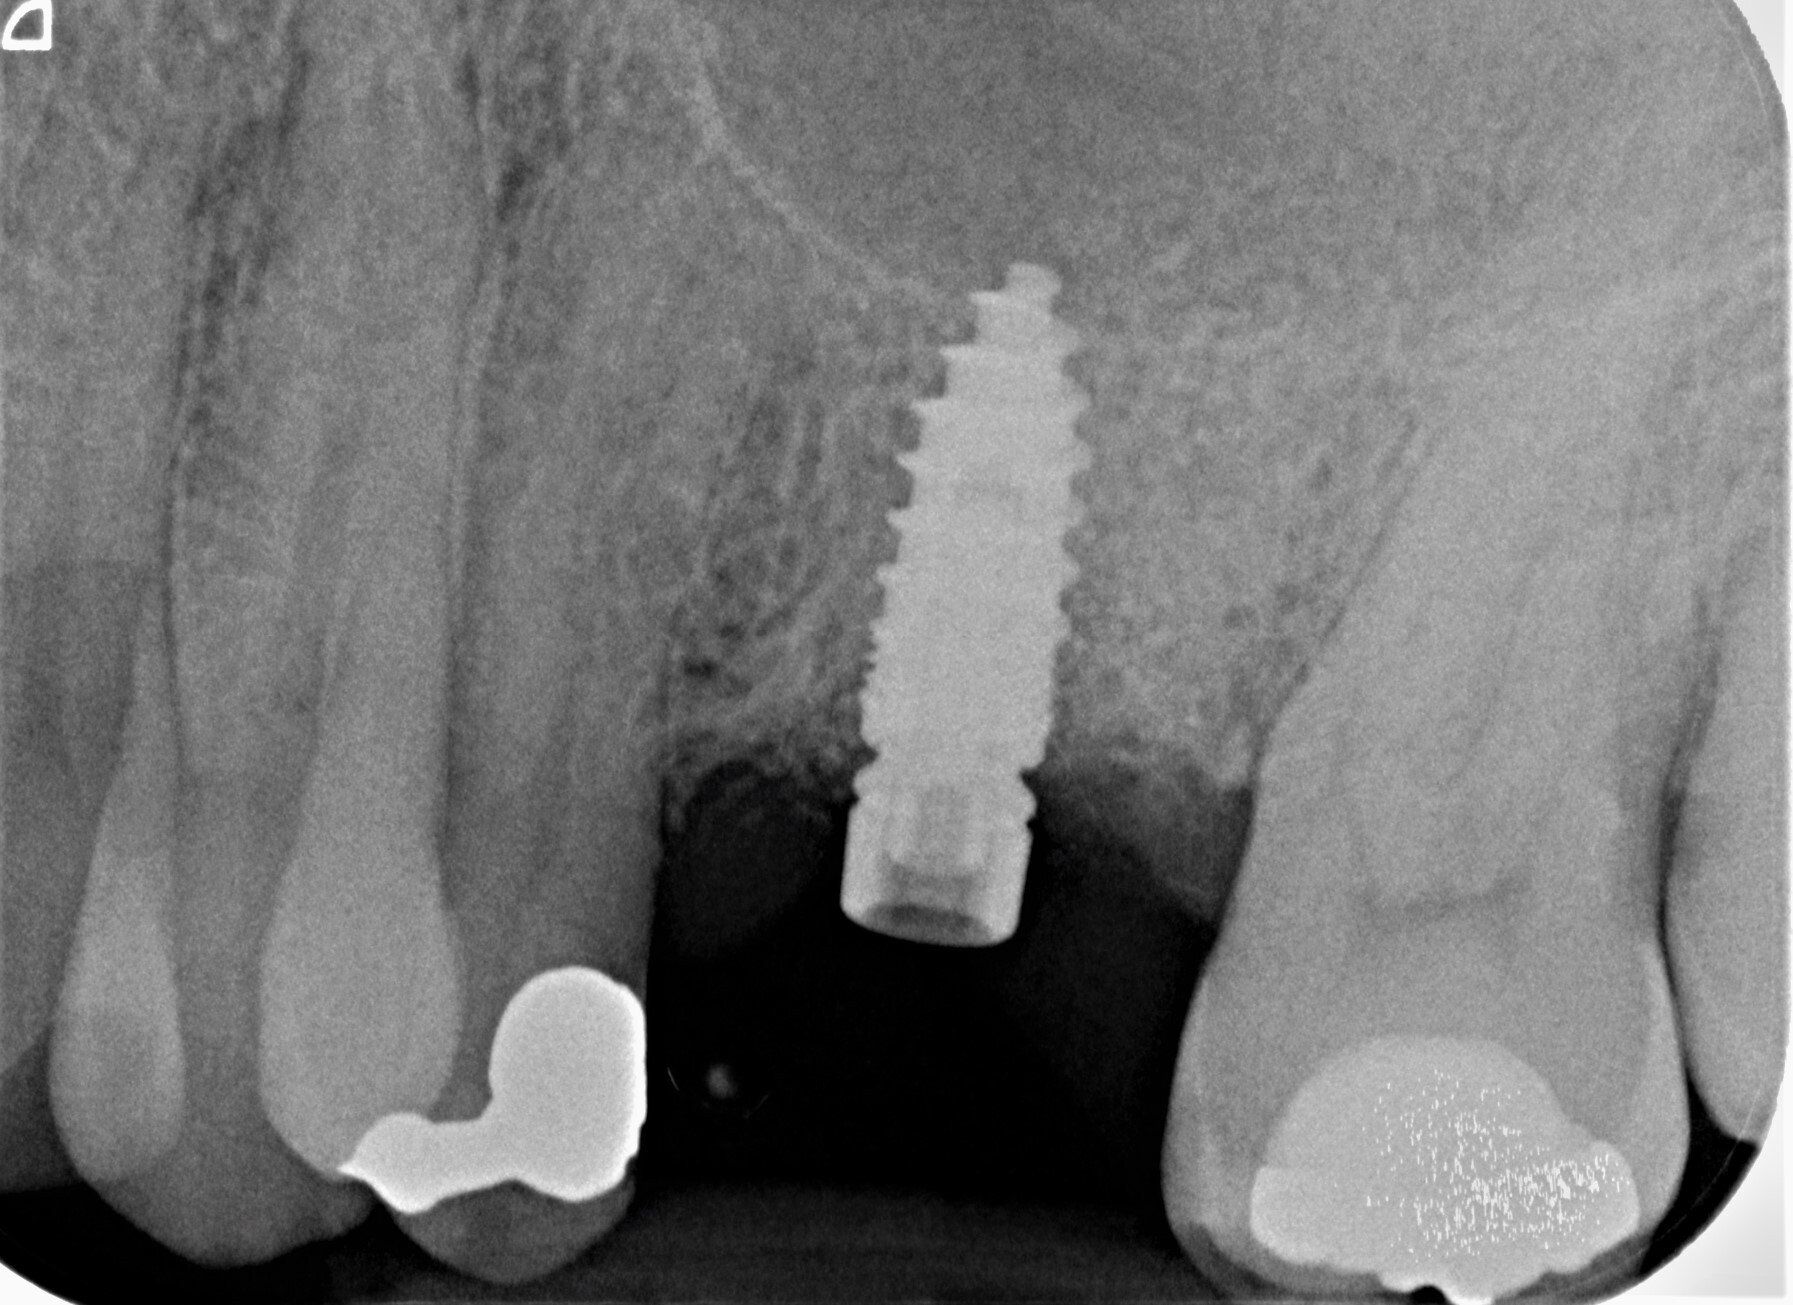

Durch den Verlust des Zahnes wandelt sich der Kieferknochen um. Nach der oberflächlichen Heilung wird das knöcherne Zahnfach vom Körper rasch abgebaut. Knochen ist für den Körper ein "teures" Gewebe, und ohne die funktionelle Kaubelastung durch einen Zahn gibt es für den Körper keinen Grund mehr, das knöcherne Zahnfach zu erhalten. Allein im ersten Jahr nach der Zahnentfernung gehen 50% des umgebenden Knochens verloren! Das ist insbesondere dann von Nachteil, wenn geplant ist, später ein Implantat für den Ersatz des Zahnes zu setzen. Ohne kiefererhaltende Maßnahmen reicht oftmals der nach der Heilung verbliebene Knochen nicht mehr aus, ein hinreichend großes Implantat einzusetzen bzw. dieses auch ideal zu positionieren.

Aus diesem Grund war jahrelang der Goldstandard zum Ersatz von Knochen - körpereigener Knochen! Dieser musste in verschiedenen Spenderregionen "gewonnen" werden, was für den Patienten oftmals eine weitere Operation bedeutete. Allerdings war schon länger bekannt, dass das Zahnbein (Dentin) eine fast identische Mineralzusammensetzung und die gleichen Eiweißstoffe wie Knochen besitzt.

Das Verfahren ist schonend und erfordert keinen zweiten Eingriff. Materialien tierischen Ursprungs werden vermieden. Die Aufbereitung findet direkt nach der Zahnentfernung in unserem Labor statt. Nach ca. 25 Minuten kann das Knochenfach aufgefüllt werden. Der Bereich muss für zwei Wochen geschont und auf der anderen Seite gekaut werden. Es sollte zwei Tage nicht geraucht werden. Alles weitere können wir den Selbstheilungskräften unsres Körpers überlassen.

Fazit: Ein Patienten schonendes, kostengünstiges Verfahren, das die biologischen Heilungsprozesse des Körpers nutzt und hilft, die Dimensionen des Knochenfaches zu erhalten.